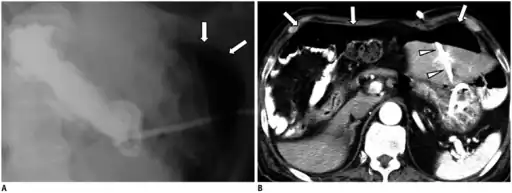

a) X-ray of abdomen, showing subdiaphragmatic free air, air outlining the properitoneal fat stripe black arrows b) Cupola sign arrowheads c) Rigler's sign d) chest radiograph showing free air under the diaphragms -

a.b)Pneumoperitoneum developed three days following percutaneous radiologic gastrostomy -